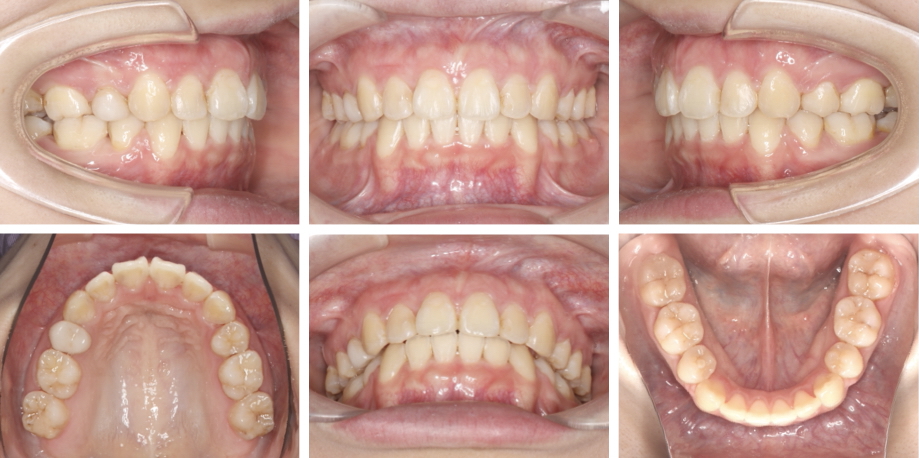

治療開始前

• 1.初診時年齢:22歳

• 2.主訴:上の前歯が出ている感じがすること、下の前歯のでこぼこ

• 3.症例のカテゴリー:叢生、上下顎前突

治療開始前、軽度の叢生と口元の突出感を認めました。主に口元の改善を目的に上下顎小臼歯2本を抜歯し治療を行う方針としました。